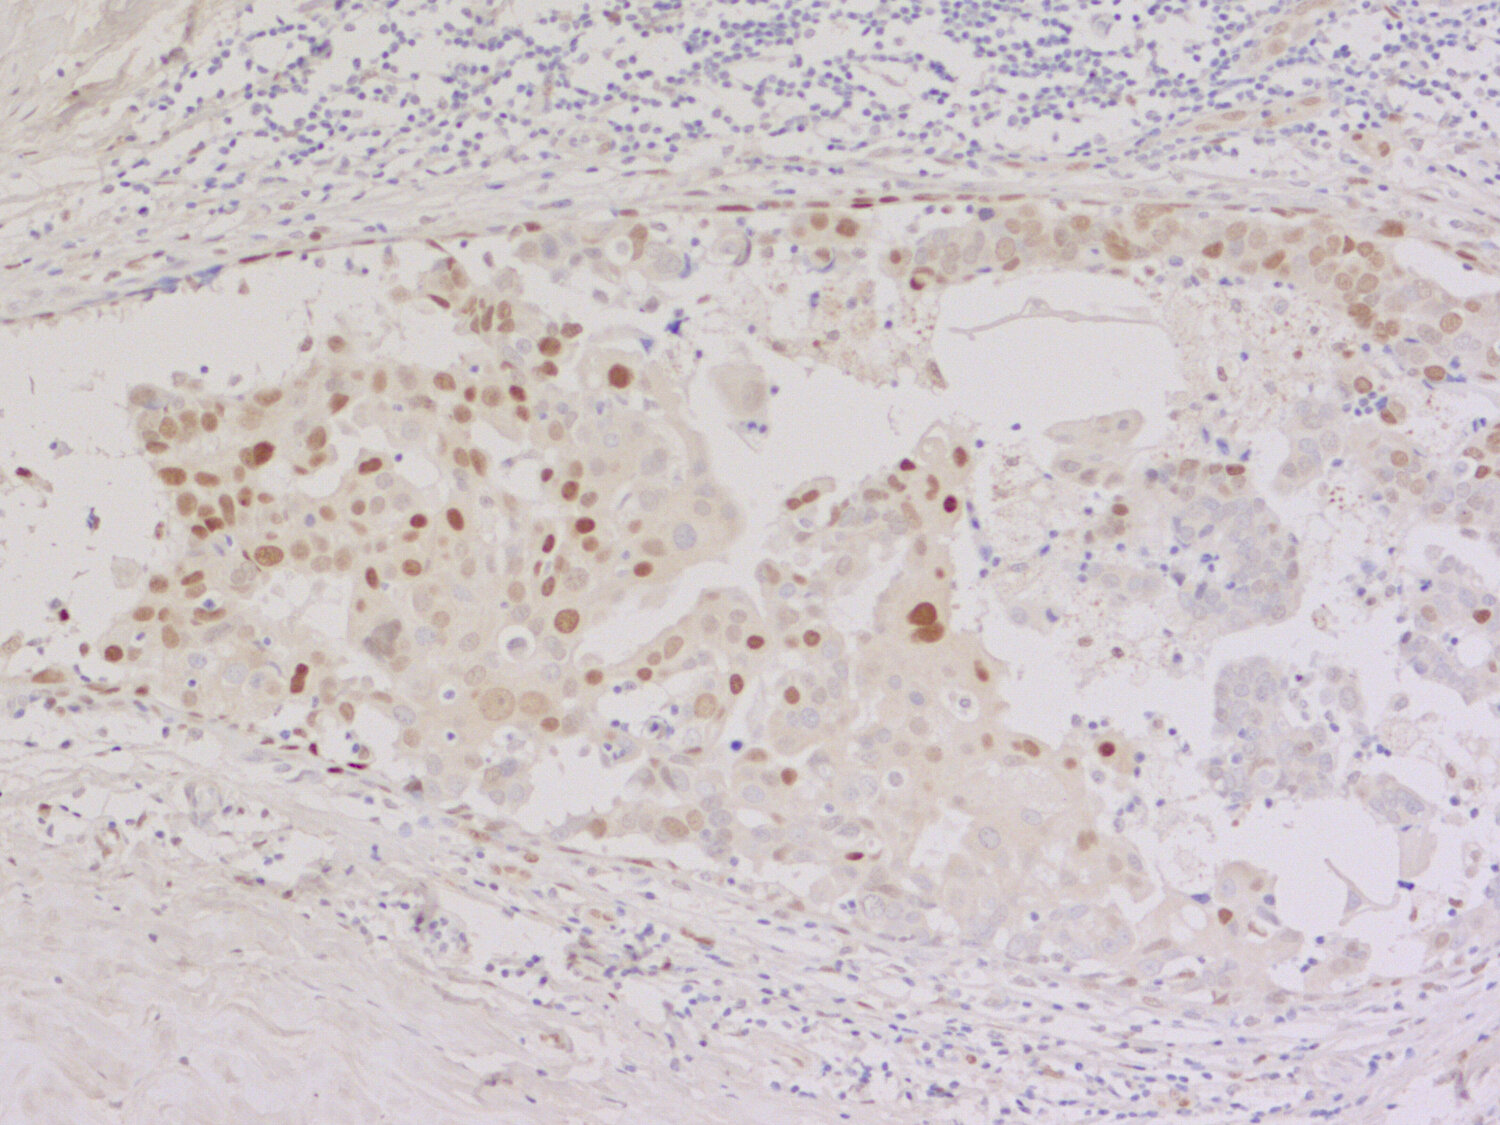

IHC: 1 : 1000 up to 1 : 5000 (see remarks) gallery

IHC-P: 1 : 100 up to 1 : 200 gallery

Immunohistochemistry (IHC-P) of formalin fixed, paraffin embedded (FFPE) tissue (some antibodies require special antigen retrieval steps, please refer to the ”Remarks” section). Immunoreactivity is usually revealed by fluorescence or a chromogenic substrate.